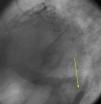

The authors present the case of an 83-year-old male with a history of hypertension, appendectomy and cervical spine surgery who presented at the emergency department with epigastric pain and dyspnea at rest for six hours. The physical examination was compatible with refractory acute pulmonary edema requiring endotracheal intubation and ventilation. The electrocardiogram showed sinus rhythm with ST-segment elevation in the inferior leads. The emergent coronary angiography revealed three-vessel disease with distal occlusion of the right coronary artery (Figure 1, Videos 1 and 2). Primary angioplasty was performed successfully (Figure 2, Video 3). During the procedure a contrast retention image was observed apparently synchronous with the cardiac/respiratory cycle (Figure 3, Video 4). The first possibility that came to mind was an aortic dissection, which was excluded by an anteroposterior projection, which showed that the image was in the midline (Figure 4, Videos 5 and 6). A chest computed tomography scan was then requested to rule out the presence of a fistula (esophageal or bronchial), which revealed that the image corresponded to retention of contrast in the medullary canal from myelography performed in the 1980s (Figure 5A and B).